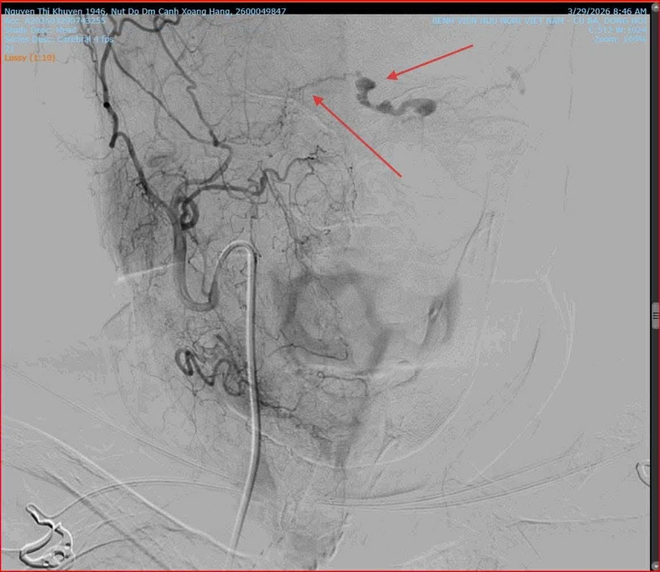

Khi thăm khám cho bệnh nhân, các bác sĩ Khoa Mắt phát hiện mắt trái của cụ K. giảm thị lực, tăng nhãn áp, lồi mắt, giãn tĩnh mạch thượng củng mạc, phù nề kết mạc, hạn chế vận nhãn. Nghi ngờ bệnh nhân bị rò động mạch cảnh xoang hang trái, các bác sĩ đã chỉ định chụp X- Quang số hóa xóa nền (DSA) và có kết quả rò động mạch cảnh xoang hang bên trái.

Nhận định đây là ca bệnh có diễn tiến phức tạp, nếu không điều trị kịp thời có thể dẫn đến mù lòa vĩnh viễn hoặc xuất huyết não, ê-kíp các bác sĩ can thiệp mạch của hai bệnh viện đã quyết định thực hiện phương pháp can thiệp nội mạch nút lỗ rò. Dưới sự hỗ trợ của hệ thống chụp mạch số hóa xóa nền (DSA), các bác sĩ đã khéo léo đưa ống thông (microcatheter) từ động mạch đùi lên vị trí tổn thương tại xoang hang.

Các bác sĩ đã can thiệp nút lỗ rò động mạch cảnh xoang hang dưới sự hỗ trợ của hệ thống chụp mạch số hóa xóa nền (DSA).

Tại đây, vật liệu can thiệp Coil và keo sinh học được đưa vào để bít kín lỗ rò một cách chính xác nhất, giúp tái lập lại dòng chảy bình thường cho mạch máu não. Ca can thiệp diễn ra thành công tốt đẹp.

Vị trí rò động mạch (ảnh trái) và sau khi can thiệp bít lỗ rò (ảnh phải).